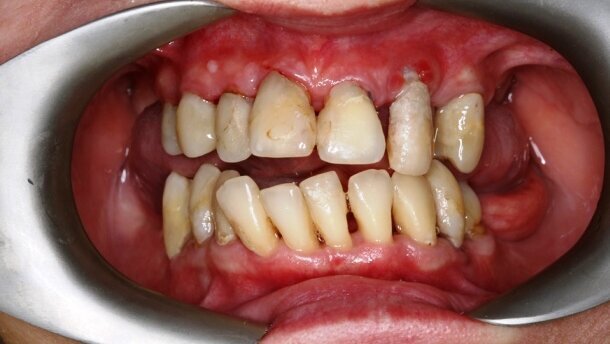

Przedstawiono obraz kliniczny wyjściowy 47-letniej pacjentki ze zdiagnozowaną zaawansowaną uogólnioną chorobą przyzębia, licznymi brakami zębowymi, brakiem protetycznego uzupełnienia zębów bocznych, zmianami okołowierzchołkowymi, niepełnym leczeniem endodontycznym. Pacjentka wymagająca kompleksowego leczenia stomatologicznego. Aby stworzyć wyjściowy plan leczenia, konieczne jest wdrożenie leczenia wstępnego (faza higienizacyjna), aby sprawdzić motywację pacjentki do dalszego leczenia wysokospecjalistycznego i ocenić rokowanie zębów.

Po higienizacji stan kliniczny pacjentki poprawił się. Wykonano kontrolne badania obrazujące zaawansowanie choroby przyzębia.

Następnie zastosowano laser Nd:YAG do sterylizacji kieszeni przyzębnych, dekontaminacji (Ryc. 3-7) i laser Er:YAG do usunięcia kamienia poddziąsłowego (Ryc. 8-12) oraz ponownie laser Nd:YAG do stabilizacji skrzepu (Ryc. 13 i 14). Na rycinie 15 przedstawiono stan bezpośrednio po zabiegu usunięcia kamienia poddziąsłowego laserem Er:YAG wraz ze sterylizacją kieszeni przyzębnych laserem Nd:YAG (LightWalker, Fotona).